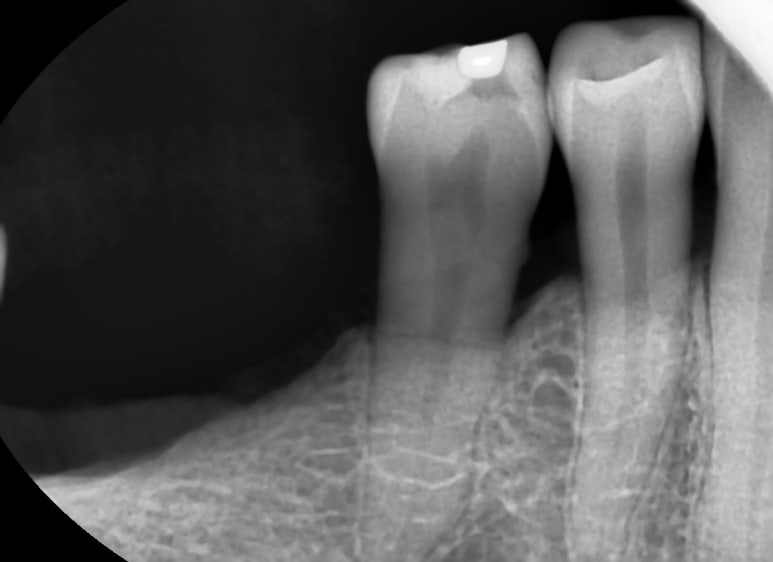

엑스레이를 촬영 해 보니 이미 큰 어금니는 싱가폴에서 많이 발치한 상태 였고

이번에는 작은 어금니가

가로로 파절된 것이 의심되는 확인할 수 있었습니다